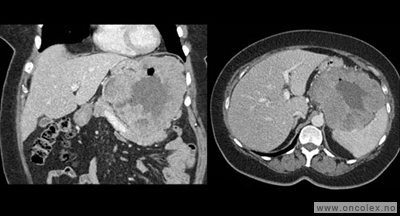

På grunn av den spesielle lokalisasjon oppdages svulstene ofte sent, og de er gjerne store på diagnosetidspunktet.

• CT toraks, buk og bekken er standard utredningsmetode ved svulst i buken og på bakre bukvegg, og kan gjøres ved lokalsykehus. De viktigste fordelene ved CT er at undersøkelsen tar kort tid. Innføringen av spiral-CT, og spesielt multislice-teknikk, har forbedret kvaliteten. Røntgen av lungene er som regel tilstrekkelig for å oppdage eller utelukke spredning til lunge.

Typiske funn

Bildeeksempler